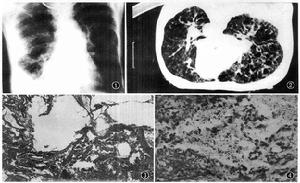

胸部影像學

(一)胸部X線片

淋巴管平滑肌瘤淋巴管平滑肌瘤患者的胸片所見差異較大,早期可無明顯異常,或表現為磨玻璃影。隨病情發展漸出現瀰漫性小結節,從粟粒狀到中等大小的結節狀或網狀結節影,同時有不規則的網紋和線條狀陰影,多呈均勻性分布。這些陰影可能是多發性囊腔壓迫過度增生的平滑肌所致。早期肺容積正常。隨病情發展肺野中可見模糊不清的少量囊性變,一般囊腫直徑>1cm時胸片才能顯示。大量肺囊腫形成可使肺容積明顯增大,與肺氣腫相仿、淋巴阻塞可形成KeleyB線。同時可見單側或雙側胸液,常為乳糜性,量較多而且反覆發生。乳糜胸液也可發生在肺未受累的情況下,自發性氣胸發生率高,淋巴管造影可發現腹後壁病變。

(二)胸部CT和HRCT

是診斷淋巴管平滑肌瘤的重要手段。胸部CT尤其是HRCT可以明確顯示出普通胸片顯示不清的肺囊腫。淋巴管平滑肌瘤的肺囊腫具有顯著特點,為全肺均勻分布的大小不等的薄壁囊腫,直徑在0.5~5cm之間,囊壁的厚度一般<2mm。早期囊腫較小,隨病情發展囊腫加大。這類形態的囊腫發生率為100%,是診斷淋巴管平滑肌瘤的重要依據。早期約50%患者出現磨玻璃影。在CT上能看到結節陰影者僅5%左右,為腫大的囊腫壓迫周圍過度生長的平滑肌細胞所致。如出現片狀陰影則提示出血。Sherrier等報告的8例LAM患者中4例發現縱隔淋巴結腫大。以HRCT定量測定囊腫面積與測定肺容量、彌散功能、運動試驗所評價的疾病嚴重程度相符合,故HRCT即可用於診斷又可判定預後。CT或HRCT可發現腹後壁、腹腔、腎臟、盆腔的病變。